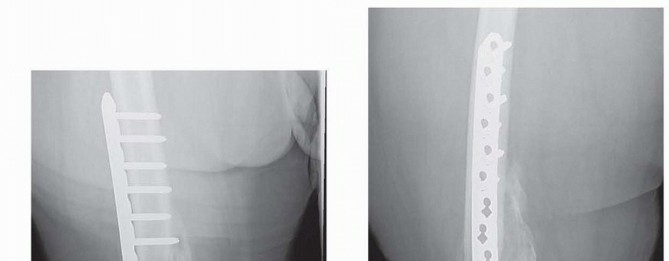

### FIG 9 • Critically ill elderly polytrauma Jehovah's witness patient with left C1 distal femur fracture. A,B. Initial injury AP and lateral views. C,D. Due to extremely low hematocrit, external fixation was the only surgical option allowed to minimize blood loss. Radiographs in bridging external fixation. The AP shows excellent alignment but the lateral shows the expected extension deformity secondary to pull of gastrocsoleus complex. E,F. After 5 weeks in an external fixator, AP and lateral radiographs show callus formation (red arrows). Patient is now cleared for definitive surgical intervention. Antegrade intramedullary nailing has been described and can be used for distal fractures with a large enough distal segment to allow for two locking screws. Malalignment has been a problem, as has adequate fixation. 4, 8 Retrograde intramedullary nailing can be used in the following cases ( FIG 10): All extra-articular type A fractures greater than 4 cm from the joint. This minimal length of the distal femur allows for multiplanar interlocking in the distal fragment. Type C1 or C2 fractures where the articular fracture can be anatomically reduced closed or with limited exposure. Percutaneous screws are used for the articular injury. Periprosthetic fractures around a total knee arthroplasty with an “open box” femoral component Most surgeons prefer to use a long nail, but short supracondylar nails are available as well. Multiple-hole short supracondylar nails have fallen out of favor. Plate fixation ORIF with plates can be used for all types A and C fractures but is ideal for the following injuries: Very distal type A fractures within 4 cm of the knee joint All articular type C fractures, but always for C3 types Periprosthetic fractures about a “closed box” femoral component of a total knee arthroplasty The partial articular type B1 or B2 if an antiglide plate is needed Plate options (preferred to least preferred; fixed-angle devices preferred) Fixed-angle locking plates (percutaneous jigs are advantageous and allow for minimally invasive techniques) Variable-angle (polyaxial) locking plates—allow for “fixed variable locking” within a defined range. It is useful for distal fractures and allows for increased screw 473 trajectories to gain additional locked fixation in short segments, which may not be feasible with fixed-angle trajectory plates ( FIG 11).

### FIG 10 • A,B. AP and lateral radiographs of an elderly patient with multiple comorbidities with an extra-articular distal femur fracture (AO type A; an incomplete intercondylar split— red dashed arrow). C,D. Postoperative radiographs showing stabilization with retrograde intramedullary nail. E,F. One-year postoperative radiographs showing a healed fracture with some subsidence of the metaphyseal region and mild protrusion of hardware through the notch. Ninety-five-degree condylar screw Ninety-five-degree blade plate Nonlocking plates with or without medial support (medial plate or external fixation) Limited internal fixation Limited fixation with screws only can be used for partial articular type B, especially type B3. The amount of open reduction required depends on the adequacy of closed reduction techniques and obtaining an anatomic reduction of the joint surface. Headless screws are useful for type B3 fractures in which the screws have to penetrate the joint surface ( FIG 12). Countersinking the screw heads can also be performed. Biomechanics of fixation: implant considerations There has been concern that the newer locking plate constructs are too stiff, resulting in inconsistent and asymmetric callus formation. 9 Some clinical evidence show less callus formation with stainless steel plates versus titanium plates. 9 Conversely, a biomechanical study has not shown a significant difference mechanically between constructs of stainless steel LISS plates with bicortical screws or titanium LISS plate with unicortical screws.1 474

### FIG 11 • Morbidly obese female with a severely comminuted and open right distal C3 femur fracture. A,B. AP and lateral radiographs showing the amount of comminution, bone loss, and distal nature of the injury after the initial irrigation, débridement, and bridging external fixation. C,D. Intraoperative fluoroscopic images during application of a variable-angle locking plate. The AP shows the “central screw” to aid in reestablishment of the anatomic axis of the femur (parallel lines solid , screw; dashed , joint line). The lateral view shows the central screw, which is a fixed-angle hole (arrow and circle), as opposed to the variable-angle holes (red box ; both for the combination holes and isolated variable-angle screws). E,F. Two-week postoperative radiographs. The AP view shows the proximal screws placed perpendicular (dashed arrows) to the plate even through the variable-angle portion of the combination holes, which was facilitated by the targeting device. Both views demonstrate the advantage of the variable-angle locking holes distally to allow for additional fixation in this short distal segment with a more posterior and distal trajectory (solid arrows on lateral view). The bone substitute placed for the bone defect (white pellets) are also clearly visualized. (continued) 475

### FIG 11 • (continued) G,H. Five-month follow-up films showing replacement of the calcium sulfate beads with successful consolidation of the metaphyseal comminution. The flexibility of fixation constructs can be increased by the use of a technique referred to as far cortical locking. Specialized screws are used, in which the screw locks into the plate and only engages the far cortex. This has been thought to improve fracture healing. 5 The “polyaxial” locking plates have been shown to be biomechanically sound in the management of supracondylar femur fractures. 12, 18 ## Preoperative Planning Surgical timing can be affected by the following: Soft tissue issues Medical condition of the patient Adequacy of available operative team Availability of implants The approach must take the following issues into consideration: The ability to incorporate lacerations in open fractures into the incision ( FIG 13) can be useful and should be considered. However, this is not always necessary or possible.